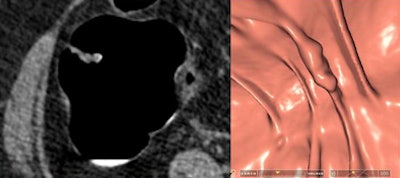

"Six lesions located on the haustral folds showed a much higher conspicuity on the 3D endoluminal views than on 2D," he said. For polyps on folds, focal thickening and surface nodularity were key features leading to their detection.

![]() |

| Six lesions detected at CAD and VC on haustral folds were more conspicuous in 3D endoluminal views (right) than on 2D (left) visualization. Key features included focal fold thickening and surface nodularity. |